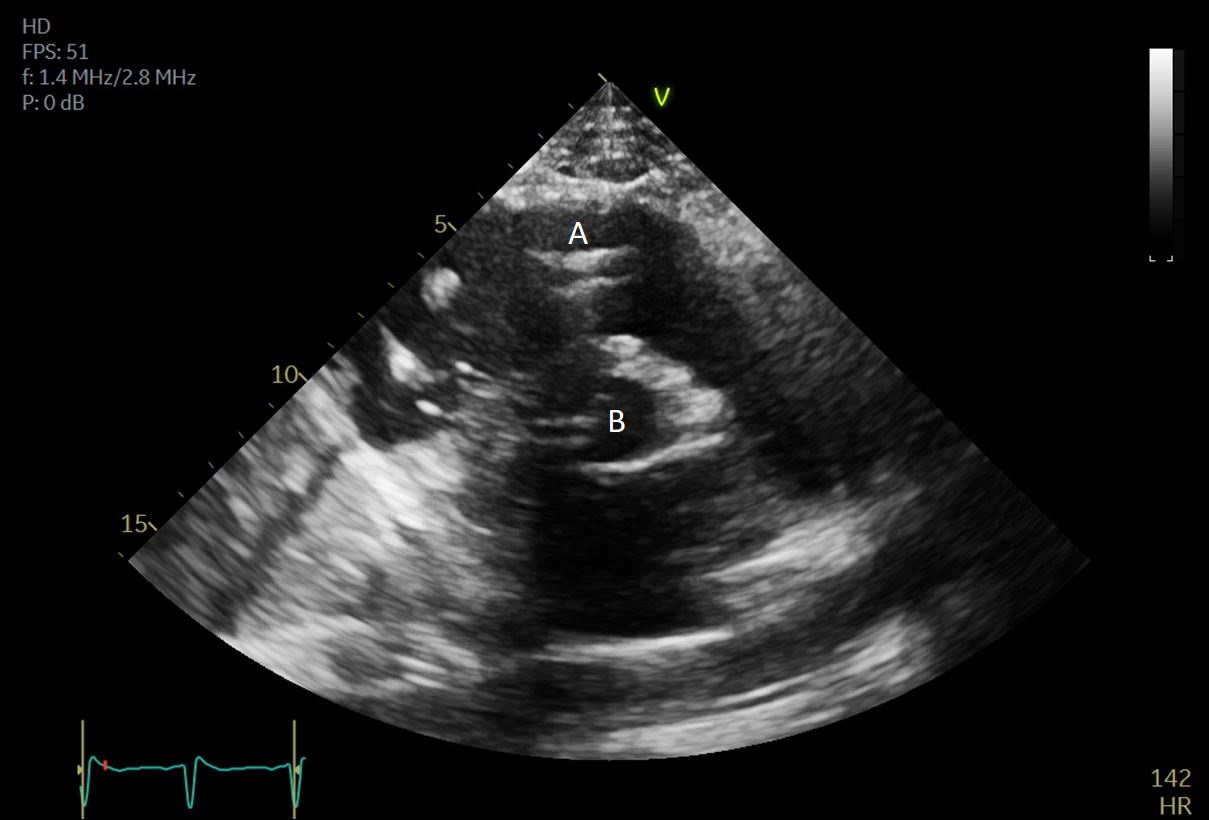

The intra-aortic balloon pump is a percutaneously placed counter pulsation device which helps in decreasing afterload as well as augmenting coronary perfusion. Initially developed in the 1960s it is the oldest MCS device and given its simplicity, cost effectiveness, and ease to implant and explant, it is the most commonly used temporary support device [6]. Although it is typically placed in the cardiac catheterization lab under fluoroscopic guidance, TEE can be utilized to help in its placement in the intubated patient in the intra-operative setting. The femoral artery is the most common site of placement however they can on occasion be placed in alternative sites such as the axillary artery or directly into the aorta [7, 8]. When placed via the femoral artery, it is threaded over a guidewire. TEE can be used to visualize both the guidewire as well as the tip of the IABP catheter during placement (Fig. 1) [9]. Ideal positioning of the balloon tip is 1–2 cm distal to the left subclavian artery to derive maximal hemodynamic benefit [10]. Positioning can be confirmed by visualizing the descending aorta and then withdrawing the TEE probe until the left subclavian artery and aortic arch are visualized. Upon activation of the balloon pump the gas filled balloon will cause shadowing and reverberation artifacts (Fig. 2). Its presence can be used as confirmation of proper function of the device. If these artifacts are not seen or bubbles are visualized in the aorta, rupture of the IABP should be suspected [9]. In addition to hemodynamic monitoring with a Swan-Ganz catheter, TTE can be used to monitor LV function after IABP placement and can help guide weaning of IABP support. It can also visualize any new or worsening aortic regurgitation. Given that IABPs work by reducing afterload, on rare occasions they can precipitate dynamic outflow tract obstruction and paradoxically worsen cardiogenic shock. Examples include patients with a relatively preserved basal or septal myocardial function in scenarios such as takotsubo cardiomyopathy or acute myocardial infarctions. Doppler imaging and color flow doppler can be used to identify such scenarios [11].

Fig. 1.TEE demonstrating IABP in descending aorta (A).

TEE demonstrating IABP in descending aorta (A) with reverberation artifact seen behind it upon activation (B).